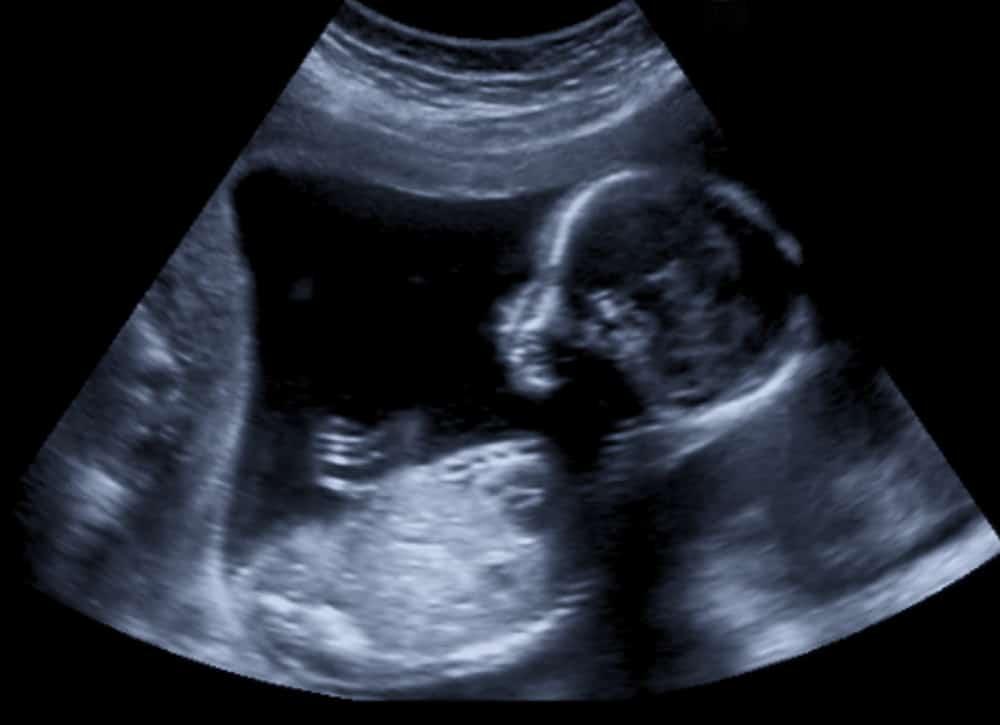

Semasa fasa janin iaitu 9 minggu selepas persenyawaan sehingga lahir, perkembangan berterusan ketika sel-sel berkembang-biak, bergerak dan berubah.

Janin terapung di dalam cecair amniotik di dalam kantung amniotik.

Janin tersebut mendapatkan oksigen dan nutrisi dari darah ibu melalui plasenta, iaitu satu struktur seperti cakera yang melekat pada lapisan dalam uterus dan berhubung dengan janin melalui tali pusat.

Cecair amniotik dan membran berfungsi sebagai bantal yang melindungi janin dari hentakan dan sentakan pada badan ibu.